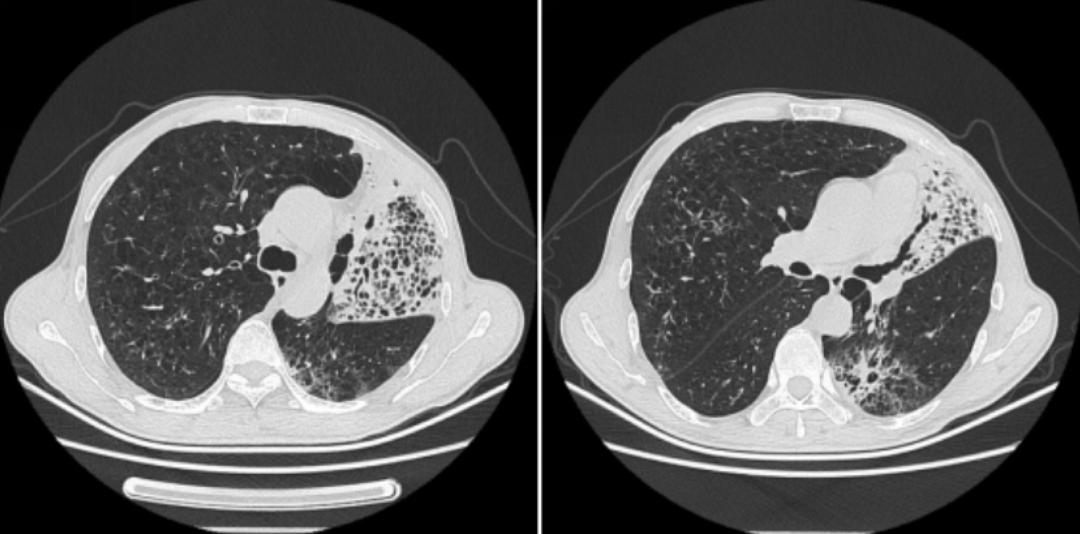

2019年3月13日,距离该患上一次住院时隔一年之后,其再次「因胸闷、气短1年余,加重1周」之主诉来我院就诊。以下为其2019年3月12日胸部CT的影像学资料:

胸部CT提示两肺间质性改变并右肺中上叶及左肺炎症,较前增多(2018年10月11日);肺气肿伴肺大泡形成;右肺中叶及两肺下叶结节,较前片变化不著;左侧胸膜增厚。

对比以上这些胸部CT,提示左肺上叶实变影变大,呈蜂窝状,左肺下叶出现磨玻璃影及少许蜂窝影。此时我们考虑患者胸部CT表现的蜂房影、囊腔影是细支气管阻塞的征像,左肺下叶磨玻璃影考虑气性播散,临床高度怀疑肺癌。